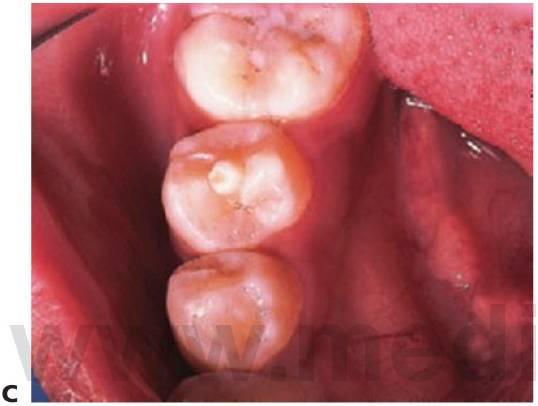

Dens evaginatus

- Un tubérculo cubierto de esmalte que sobresale de la superficie oclusal de un premolar.

- Normalmente bilateral y más frecuente en la mandíbula.

- Existen pruebas de tejido pulpar en el interior del tubérculo en el 43% de los casos.

- Las radiografías pueden mostrar la extensión oclusal de la cámara pulpar.

Tratamiento

- El tubérculo puede fracturarse fácilmente debido a las interferencias oclusales, por lo que puede resultar eficaz limar el tubérculo y sellar la fisura. Una medida profiláctica alternativa consiste en apuntalar los lados del tubérculo con resina composite y después remodelar la superficie oclusal para crear un reborde central. Esta práctica debería realizarse antes de que los dientes alcancen la oclusión completa.

- Si se fractura o se abrasiona, se suele producir una exposición pulpar y el ápice suele estar abierto debido a que dicha exposición se produce poco después de la erupción del diente, lo que empeora su pronóstico a largo plazo. Se debe proceder a la extracción del diente tras consultarlo con el ortodoncista. Si el diente se va a mantener, se recomienda llevar a cabo un procedimiento de apexificación con hidróxido de calcio (v. cap. 6) para estabilizar el diente en el caso de que la ortodoncia sea más tardía para, posteriormente, realizar un tratamiento endodóncico definitivo.

- Si se diagnostica de forma precoz, se puede practicar una pulpotomía electiva (de Cvek) en un intento de que la raíz se forme normalmente.